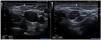

La ecografía cervical muestra vena yugular interna derecha prominente de mayor diámetro respecto al lado contralateral, con ectasia de la misma tras la maniobra de Valsalva (fig. 1). La ecografía Doppler confirma la presencia de flujo venoso y ausencia de trombos intraluminales (fig. 2).

Se diagnostica mediante ecografía y ecografía Doppler, que definen con seguridad la naturaleza de la entidad, el flujo venoso normal y la posible presencia de trombos1,2.